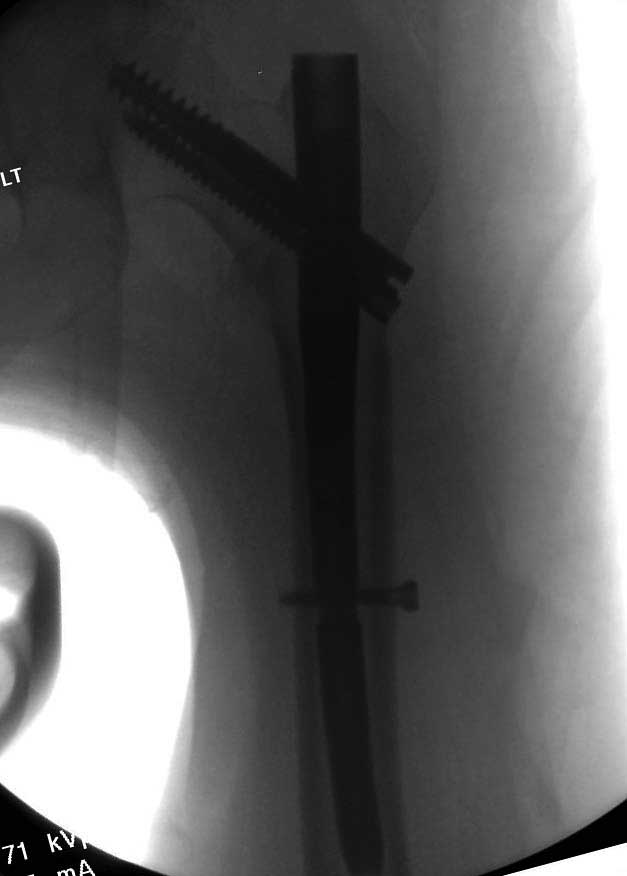

Первые снимки показывают технические погрешности установки DHS. Не была достигнута репозиция, конечность в флексии и шейка в ротации. Сегодня все меньше обращают внимание на параметры для оценки репозиции (S контуры Lowell в обеих проекциях и Garden Alignment Index, в норме 155 и 180 градусов), хотя такие простые тесты помогли бы дорепонировать смещение. Винт находится сзади в головке, что при нагрузке поменяет вектор и вместо компрессии в линии перелома срежет головку-Cut Out!

В зависимости от дистанции линии перелома и латерального кортекса надо использовать разной длины barrel, т.е. конец баррели не должен доходить до пределов перелома. Здесь конец длинного ствола упирается в медиальный фрагмент, что мешает созданию компрессии, а более короткий barrel создал бы запас для компрессии. В боковой пластине вместо 4х можно было ограничится двумя шурупами, потому что головка шурупа в 4.5 мм выдерживает давление до 350 кг.